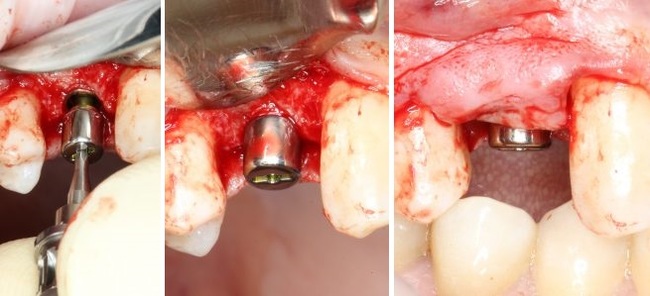

Теперь можно приступать к установке имплантата.

Имплантат нужного размера (3.8х11 мм) фиксируется на гексагональном ключе, после чего устанавливается в подготовленную лунку:

Еще раз проверяем поломжение имплантата:

Далее мы убираем временный абатмент, который в данном случае выполнял функцию имплантодержателя

Следующий этап — установка формирователя десны

С учётом клинических условий, мы подобрали к установленному иплантату формирователь Slim (без расширений) высотой 3 мм:

Заканчиваем нашу операцию наложением швов